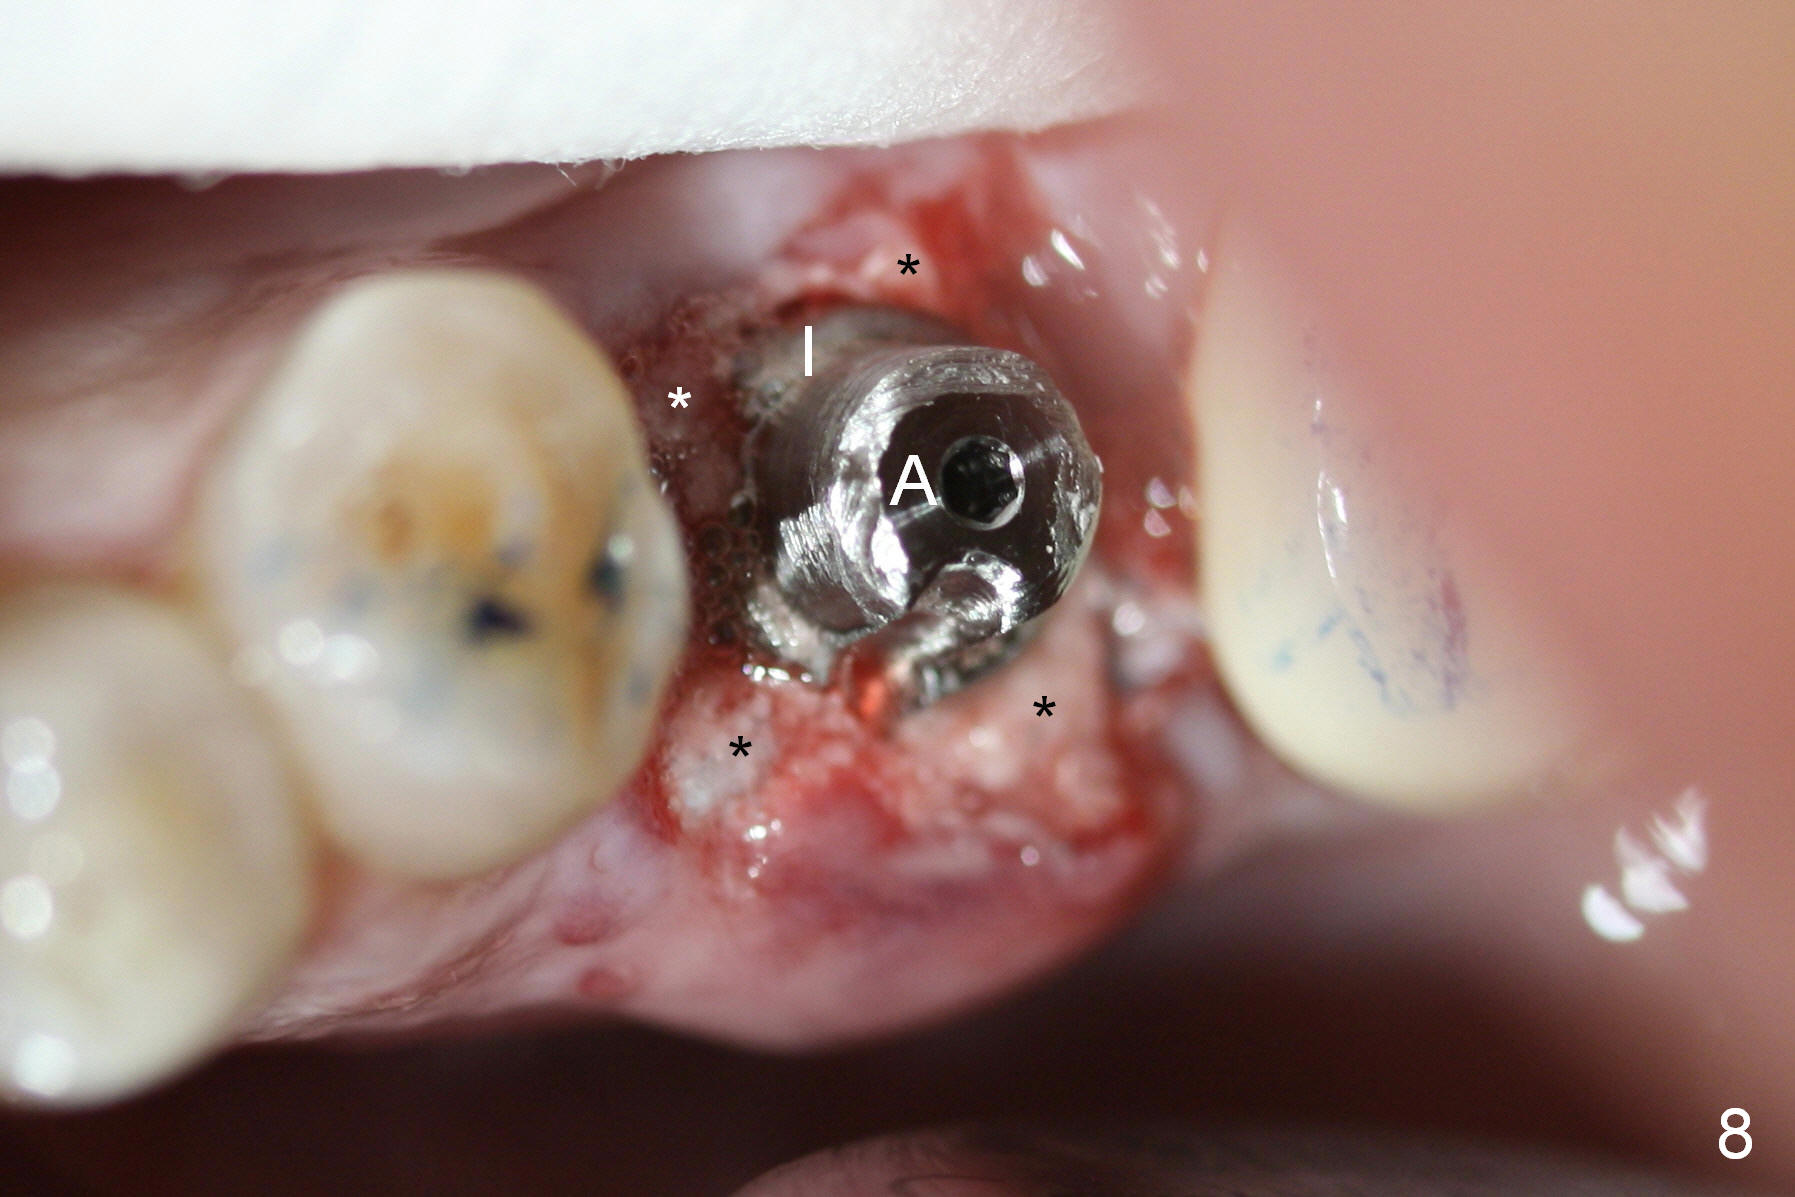

A 47-year-old lady lives out of town and presents to clinic with chief complaint "lower left back tooth easily bleeding with food impaction". Dental history and examination reveals failure of endo retreat of the tooth #19 (Fig.1), buccal gingival swelling (S), open access (A) and furcal and mesial periapical radiolucency (Fig.2 *). She is pleased to know availability of immediate implant and immediate provisional and accepts and receives the treatment at the same visit. The immediate implant (tissue-level) is designed to be as large as 7 mm and as long as 17 mm (Fig.3). To reduce paresthesia (yellow dashed line: the possible upper border of the Inferior Alveolar Canal)), a shorter implant (14 mm long in red line) is preferred. The tooth is extracted with sectioning. Granulation tissue is removed from the furca. The buccal plate appears to be intact. The septum is flat (Fig.4,10a S). Osteotomy starts in the middle of the septum with a 1.2 mm drill (Fig.10b red circle). As osteotomy increases in diameter (Fig.5 O), the apical end appears to be deviated mesiobuccally (Fig.10c large red circle). When a 6x17 mm tapered tap is being placed 14 mm deep (Fig.6 T), vibration of the buccal plate is seemingly felt at the apex (Fig.10d green circle). Further osteotomy may perforate the buccal plate. A 6x14 mm tissue-level implant is placed with >60 Ncm of insertion torque (Fig.7,8 I), followed by a 5x3 mm abutment (A) and bone graft (* in the remaining socket gap). An immediate provisional is cemented without occlusal contact (Fig.9 P).

Buccal gingival swelling and mesial periapical radiolucency suggests weakened buccal plate. Osteotomy in the septum should be initiated more lingually (Fig.10e). When the osteotomy starts being deviated, correct as early as possible with a Lindamann bur and preferably over-correct (Fig.10f blue circle). The final implant placement may not encroach the buccal plate (Fig.10f red circle). Three weeks postop, the buccal infection dissolves (Fig.11). What has not disappeared is the buccal undercut (*): the basis for potential buccal perforation. Buccolingual osteotomy trajectory should be adjusted intraoperatively accordingly.